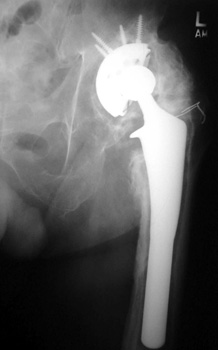

HETEROTOPIC BONE FORMATION—Fusing greater trochanter to lateral acetabulum